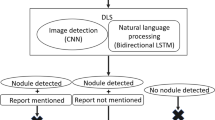

We studied a total of 101 nodules/masses detected on CT performed between January and March 2018 at Osaka University Hospital (malignancy: 55 cases). SYNAPSE SAI Viewer V1.4 was used to analyze the nodules/masses. In total, 15 independent radiologists were grouped (n = 5 each) according to their experience: L (< 3 years), M (3–5 years), and H (> 5 years). The likelihoods of 15 characteristics, such as cavitation and calcification, and the diagnosis (malignancy) were evaluated by each radiologist with and without CAD, and the assessment time was recorded. The AUCs compared with the reference standard set by two board-certified chest radiologists were analyzed following the multi-reader multi-case method. Furthermore, interobserver agreement was compared using intraclass correlation coefficients (ICCs).

The AUCs for ill-defined boundary, irregular margin, irregular shape, calcification, pleural contact, and malignancy in all 15 radiologists, irregular margin and irregular shape in L and ill-defined boundary and irregular margin in M improved significantly (p < 0.05); no significant improvements were found in H. L showed the greatest increase in the AUC for malignancy (not significant). The ICCs improved in all groups and for nearly all items. The median assessment time was not prolonged by CAD.

DL-based CAD helps radiologists, particularly those with < 5 years of experience, to accurately characterize and diagnose pulmonary nodules/masses, and improves the reproducibility of findings among radiologists.